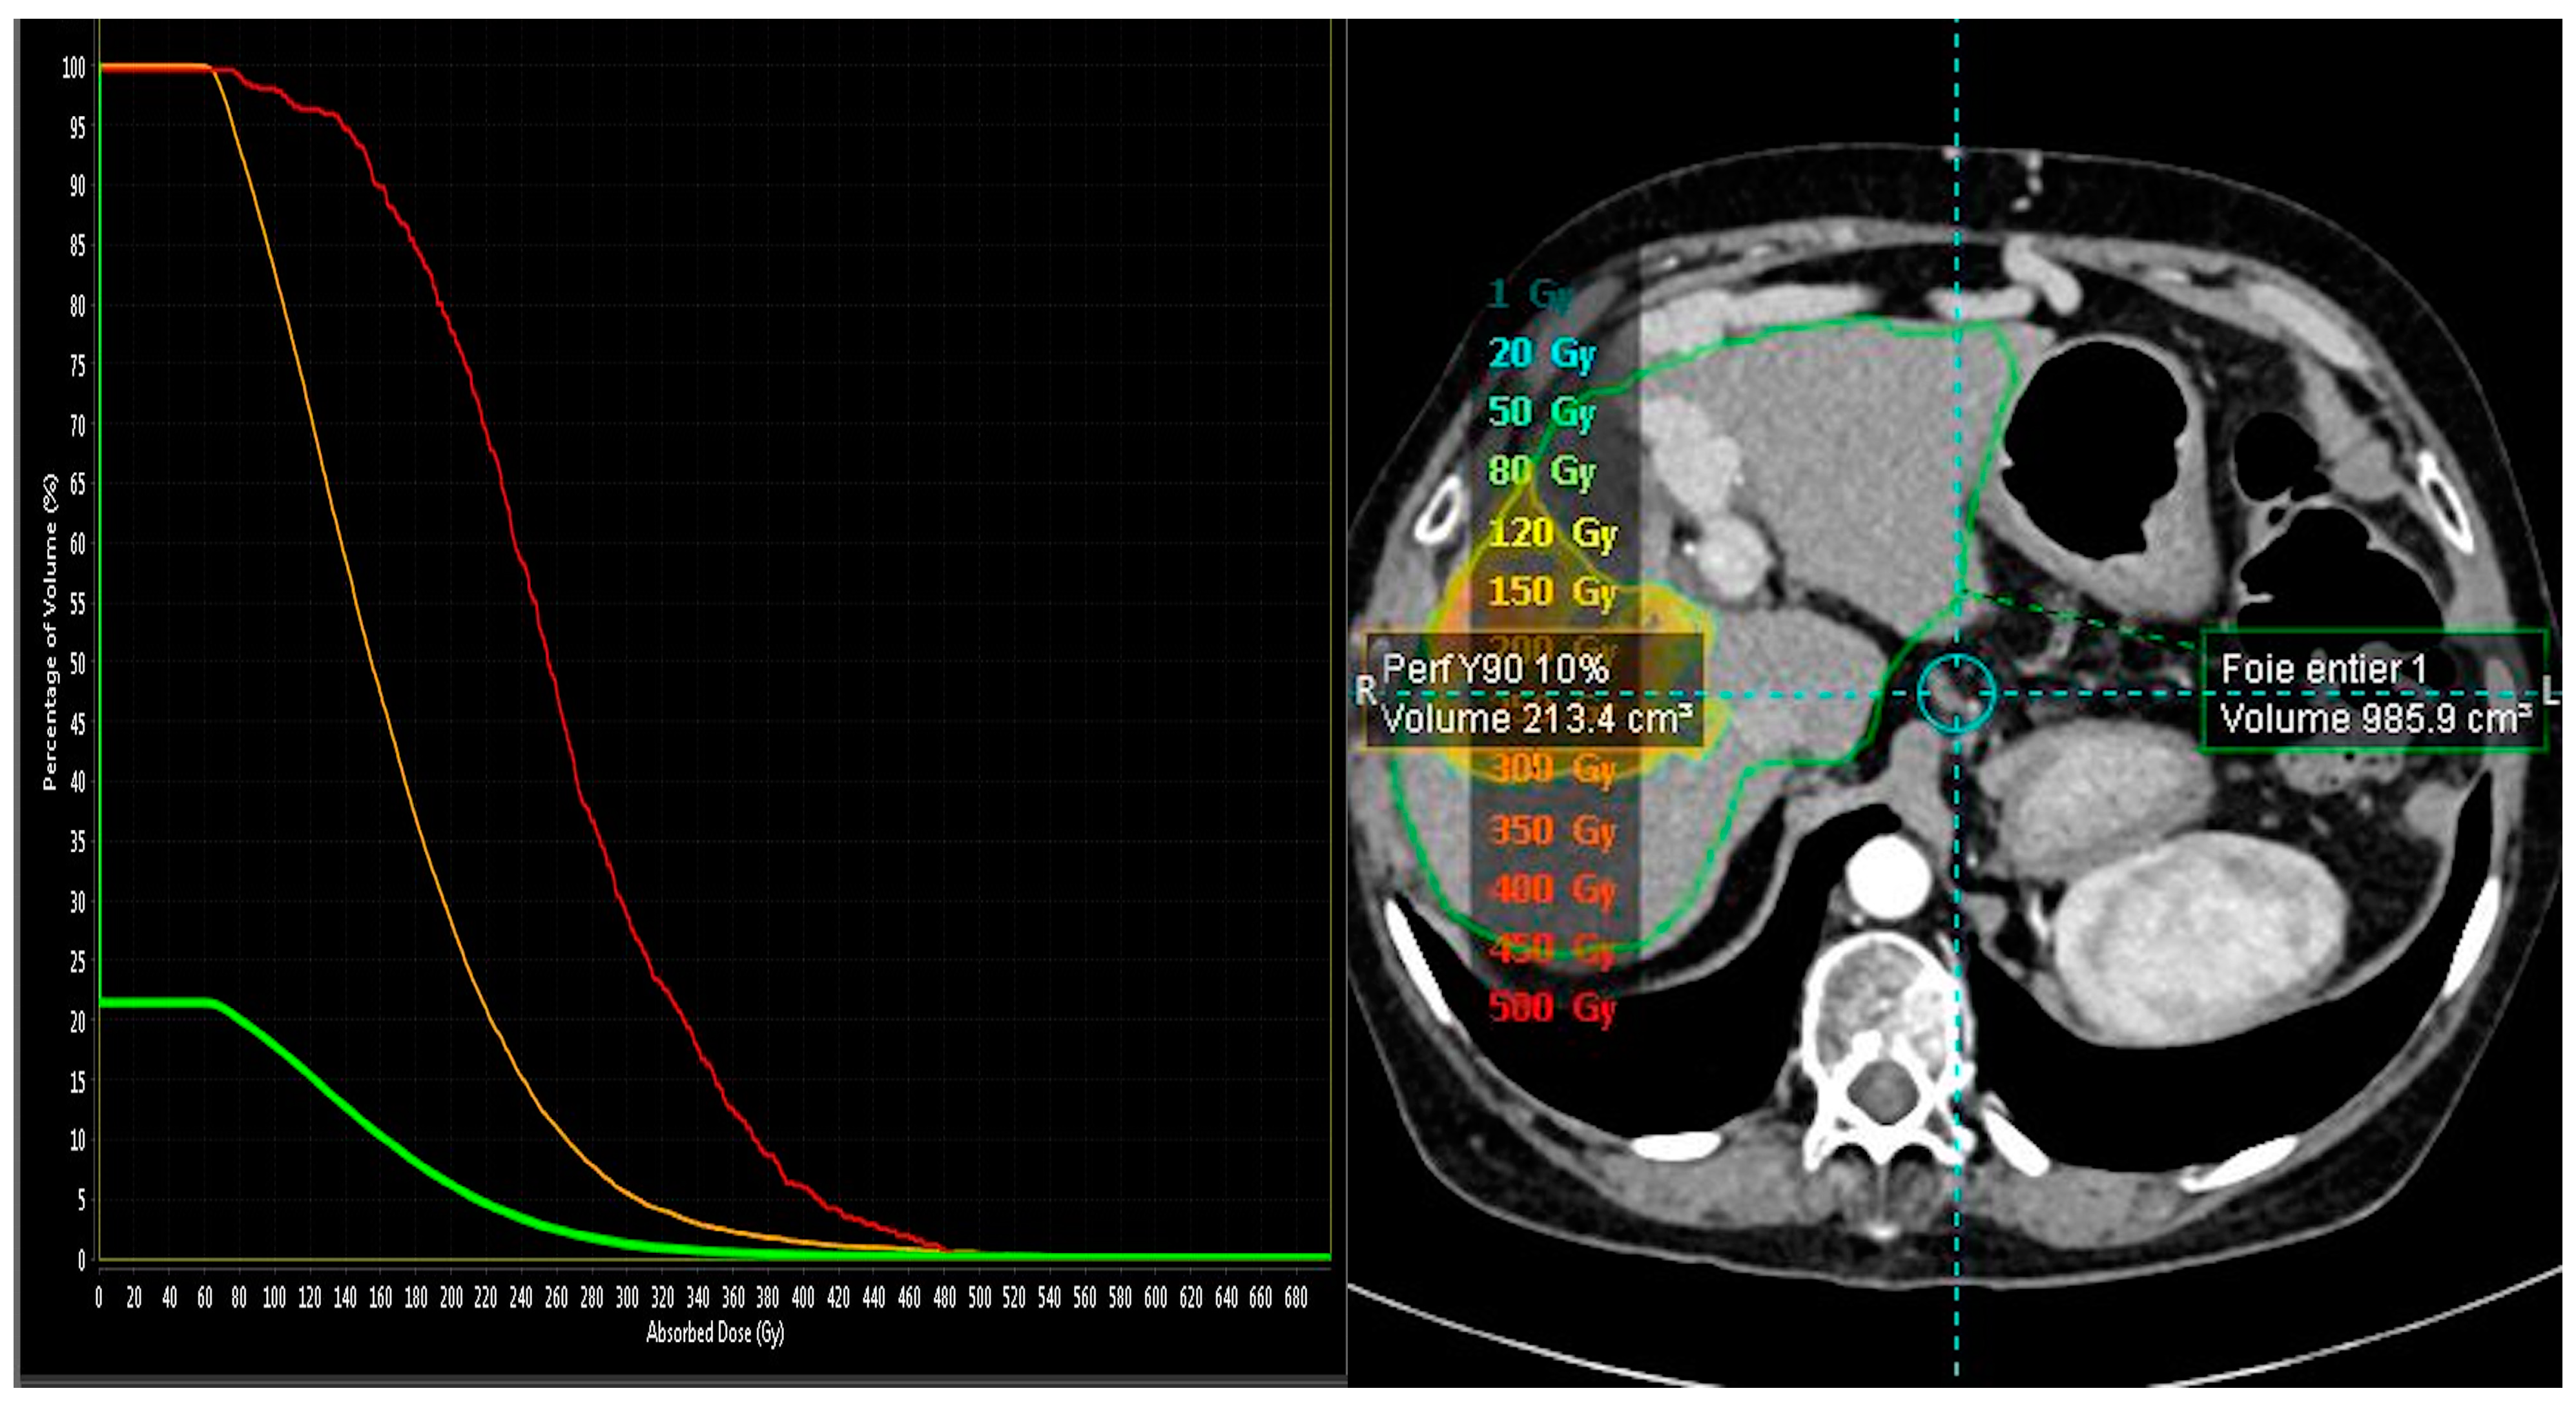

2.2. MAA-Based Dosimetry Analysis

2.3. 90Y-Based Dosimetry Analysis

| Microsphere Type/Absorbed Tumor Dose | n/(Median and IQR) |

|---|---|

| SIRT Microsphere | 23 |

| SIR-Sphere | 15 |

| TheraSphere | 8 |

| Absorbed Tumor Dose | |

| SIR-Sphere | 268 Gy (107.1–243.2) |

| For complete and partial responses n = 11 | 167.4 Gy (127.7–243.2) |

| For stable or progression responses n = 4 | 79.6 Gy (50.7–183.7) |

| Thera-Sphere | 445 Gy (349.5–563.5) |

| For complete and partial responses n = 6 | 520 Gy (422.5–587.5) |

| For stable or progression responses n = 2 | 319 Gy (288.5–349.5) |